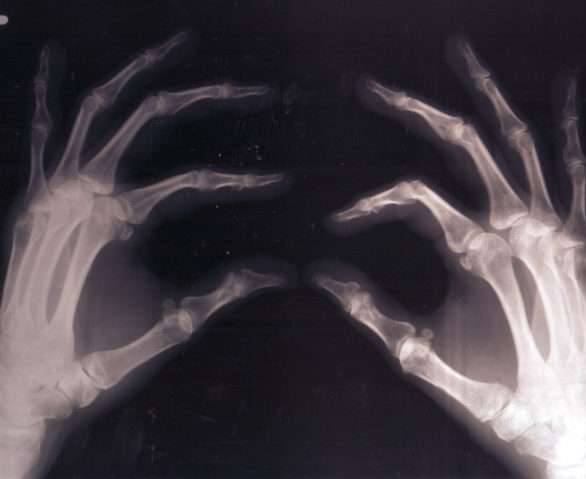

▼15. 碳酸饮料中含有磷酸,这会导致骨质疏鬆。